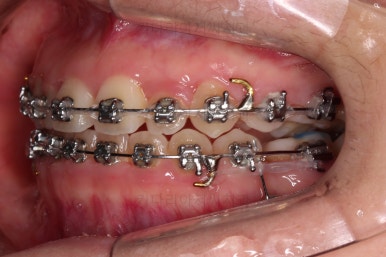

미니스크류가 등장했네요.

아랫니는 아무 생각 없이 당기기 해주면 앞니가 너무 들어가 입이 합죽해질 수 있으니 앞니가 들어가는 양을 조절하기 위해서 미니스크류를 사용해주어요.

적절한 시기부터는 어금니만 100% 앞으로 당겨와야 했기 때문이죠.

비슷한 방법으로 계속 당기기를 해줍니다.

이 과정이 매우 어렵고 시간도 많이 걸려요.